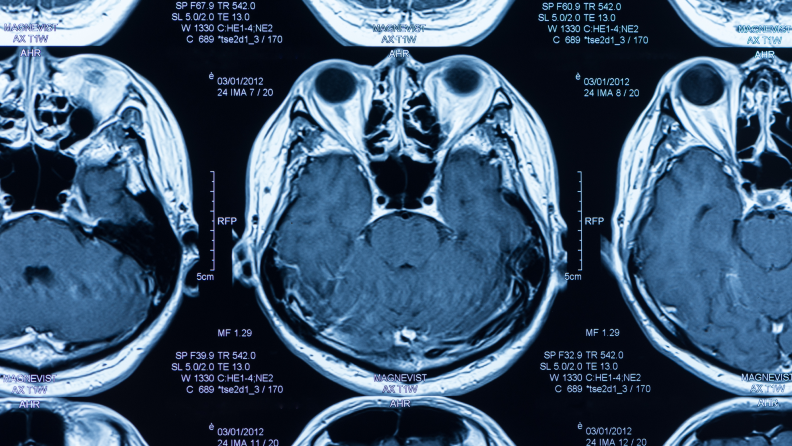

Очаговое повреждение головного мозга: синдром спастичности

Спастический парез представляет собой патологическое увеличение мышечного напряжения (мышечный гипертонус) или спазм определённых групп мышц. Результатом становится прогрессирующее ограничение мышечной подвижности, у пациентов наблюдаются различные двигательные нарушения: непроизвольные резкие движения конечностей, судороги, скованность, невозможность свободно выполнять ранее привычные действия. Нарушается координация, осанка, походка, пациент может чувствовать боль. В конечном итоге не только существенно страдает качество жизни, но и становится невозможной полноценная реабилитация.Современная медицина рассматривает спастику не как самостоятельное заболевание, а в качестве синдрома поражения центральной нервной системы, возникающего вследствие очаговых повреждений головного мозга, спинного мозга и ряда других причин.